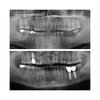

Implant Treatment